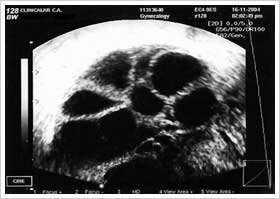

Esta fotografía es un ejemplo de este medicamento. Es probable que no se muestren todas las fotografías del medicamento. Leer más »